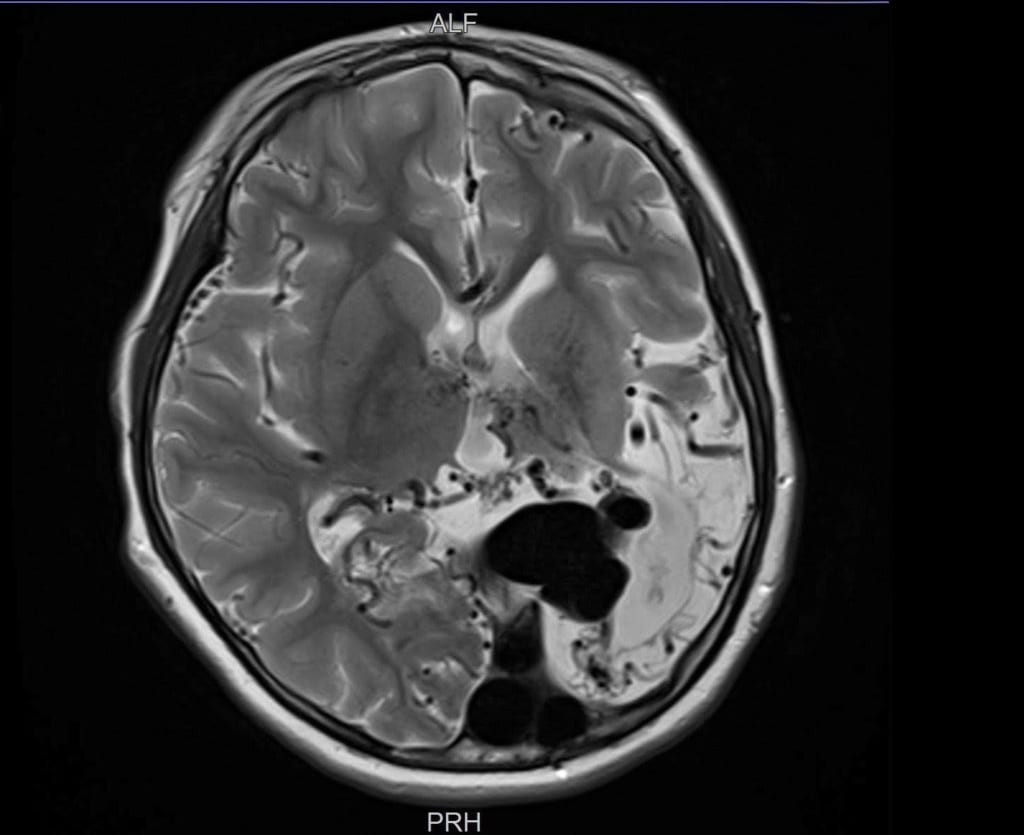

Ngay khi chào đời tại Bệnh viện Nhi Đà Nẵng, bé N.P.T.D đã rơi vào tình trạng tím tái, suy tim cấp, suy hô hấp nặng. Các bác sĩ phát hiện trong não bé có khối dị dạng mạch máu não bẩm sinh, có nhiều động mạch nuôi phức tạp và lưu lượng máu chảy qua rất cao.

Các chuyên gia đầu ngành trong và ngoài nước đã hội chẩn, đều nhận định đây là trường hợp dị dạng mạch máu não khá lớn và phức tạp, rất khó để can thiệp.

Khi bé D. vừa tròn 1 tuổi, TS.BS Trần Chí Cường đã có ca can thiệp đầu tiên cho bé tại Đà Nẵng. Các bác sĩ trong ekip can thiệp cho biết: Lần can thiệp này là một thử thách lớn, trong khi khối dị dạng phức tạp thì bệnh nhi lại còn quá nhỏ, dụng cụ can thiệp hạn chế.

Sau nhiều nỗ lực, lần can thiệp đầu tiên đã thành công, vượt ngoài sự mong đợi. Chiến lược can thiệp được các bác sĩ hội chẩn là can thiệp nhiều lần cho bé để giảm nhẹ, giảm nguy cơ vỡ khối dị dạng. BS.CKI Dương Hoàng Linh, đơn vị can thiệp DSA, bệnh viện S.I.S Cần Thơ chia sẻ thêm:

Suốt 10 năm, bé D. đã trải qua 8 lần can thiệp mạch não. Mỗi lần là một cuộc chiến sinh tử, đòi hỏi bản lĩnh và sự tận tâm của đội ngũ y bác sĩ cùng niềm tin mãnh liệt từ gia đình.